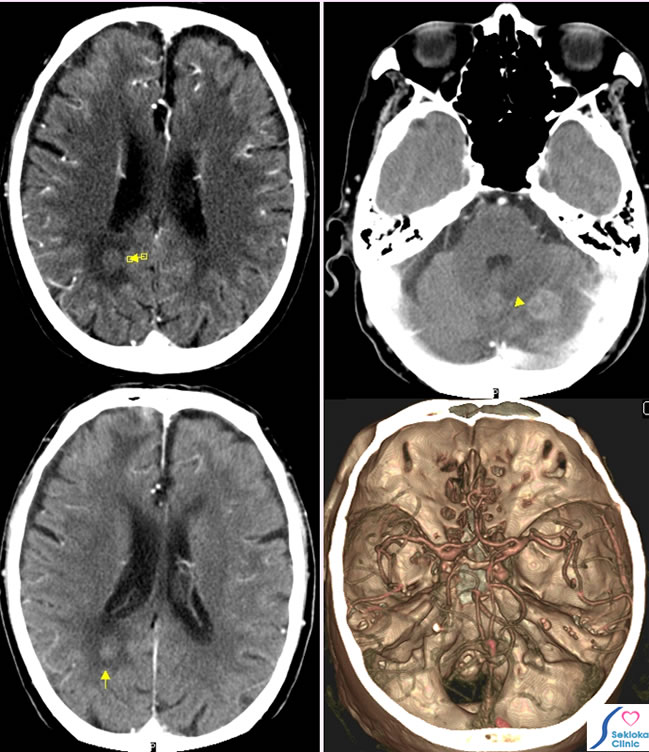

脳腫瘍(転移性)

症状

食欲不振、意識障害、歩行障害

診断

症状と他の部位に進行がん認めたため、転移性脳腫瘍疑い造影CT施行

治療

他の部位の進行状況から放射線療法と保存的治療